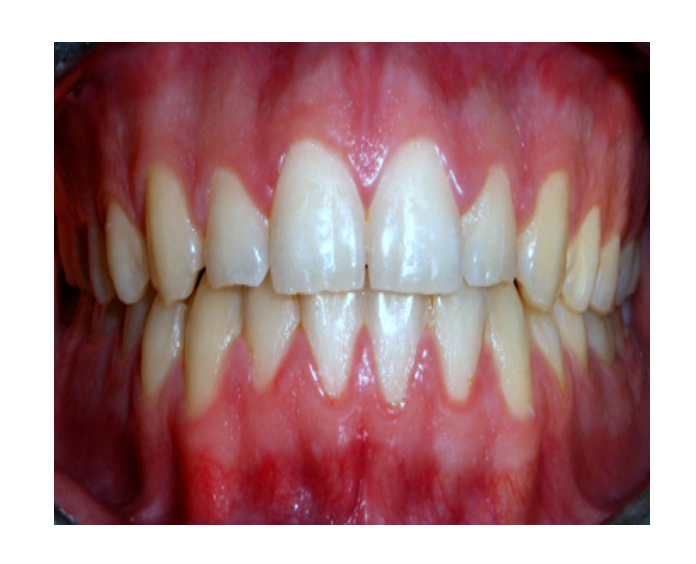

Ortodoncia en

Adultos